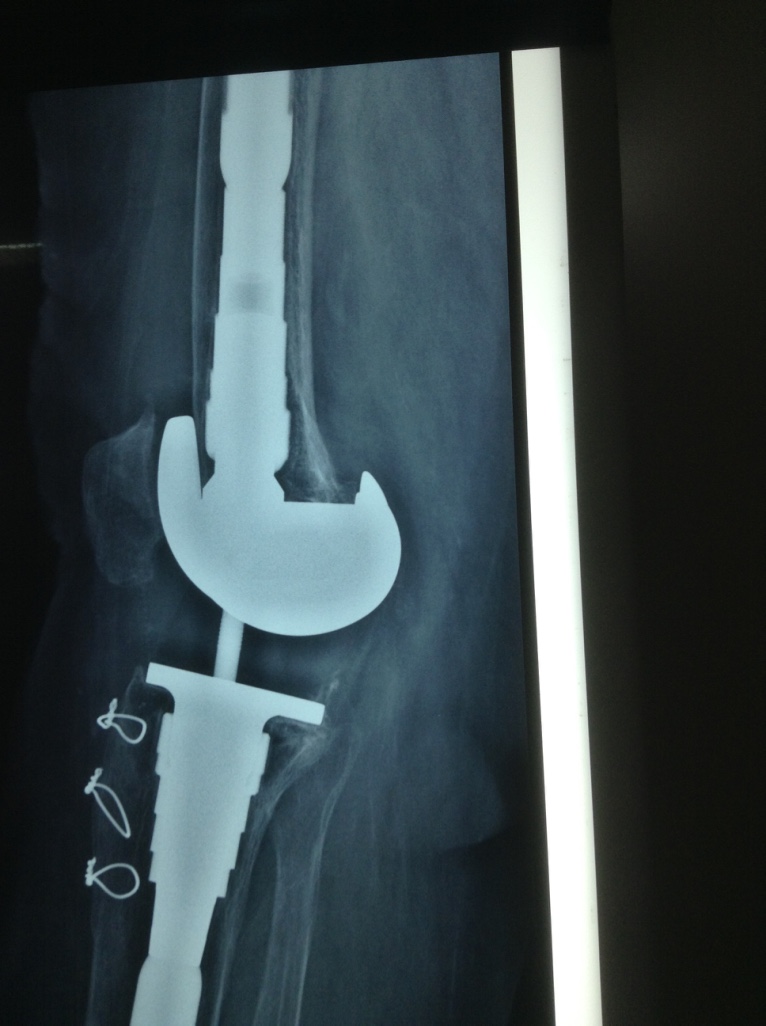

Revision Total Knee Replacement After a fructure

• Revision Total Knee Replacement After a fructure